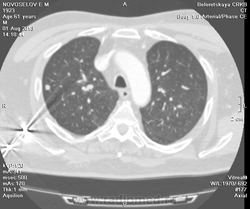

Метастазов в легкие не вижу. Похоже на лимфоузел в головке левого корня. Если позволите, запаздываете с началом исследования, плотность контраста в легочных артериях должна быть выше, чем а аорте. А одышка, не мудрено, легочная ткань диффузно уплотнена по типу "матового стекла", написал бы какую-нибудь интестициальную пневмонию, по типу альвеолита, может быть и гиперчуствительный пневмонит (не разберу есть или нет внутридольковые очажки), посмотреть бы изначально легочное окно, а не восстановленное из мягкотканного.

В диф. ряд: саркоидоз, атипичная форма.

Кажется,я понял,что Вы имели ввиду.Очажки стрелочкой указал.Согласен с тем,что очаги на фоне отображеничя сосудов кажутся фантазией,но они присутствуют.

Коллега, вынужден извинться и дезавуировать свой первый пост. Пересмотрел. Да, есть очаги, и они - вероятнее всего, метастазы.